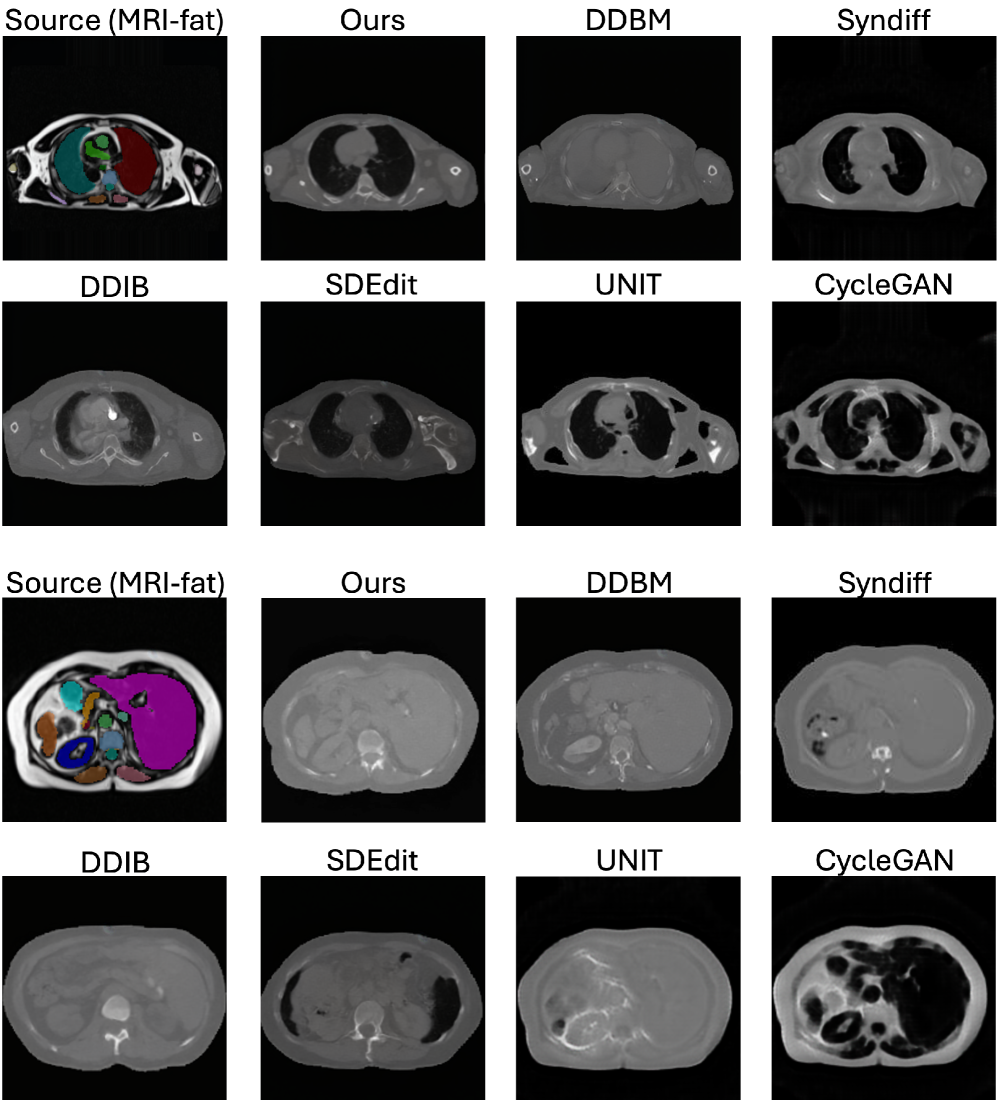

Refer to caption

Figure 4: Our SSB ensures anatomically consistent MRI\rightarrowCT translation across in-domain and out-of-domain scenarios. Segmentation masks are overlaid on MRI source images in OOD settings to provide structural reference, as paired CT ground truth is unavailable. They are not used during training or inference and serve only to illustrate anatomical fidelity without segmentation supervision.

We compare our method against representative baselines widely used in medical I2I translation, including GAN-based models CycleGAN Zhu et al. (2017) and UNIT Liu et al. (2017), zero-shot diffusion approaches SDEdit Meng et al. (2022) and DDIB Su et al. (2023), and the hybrid CycleGAN–diffusion framework SynDiff Özbey et al. (2023a). Since edge-based representations, such as Canny edges, are commonly used in MRI–CT translation—where diffusion models learn to reconstruct images from edge maps in a self-supervised manner Chen et al. (2024)—we additionally implement a DDBM variant using Canny edges. This comparison demonstrates that DINO-based embeddings capture richer geometric and semantic information than handcrafted edge filters. Fig. 4 and Table 1 present qualitative and quantitative results on in-domain and OOD MRI\rightarrowCT translation. Since no paired CT is available, we compute FID against CT scans from the training set and MS-SSIM between the input MRI and the synthesized CT as a proxy for structural similarity. We also provide qualitative results and segmentation overlays, with additional visuals in the Appendix. Our method shows stronger robustness to new MRI contrasts and achieves more accurate translations than SynDiff and DDBM, preserving geometry and modality realism.